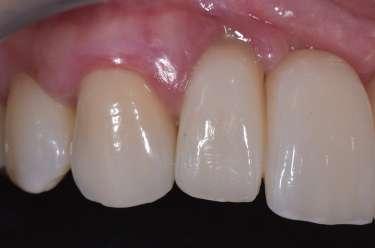

Paziente femmina, 38 anni che presenta carie cervicale dell’elemento 1.5. Gengivectomia con manipolo angolato, tip in zaffiro con diametro di 400 μm, lunghezza 12 mm, 2.4 W, 20 Hz, 120 mJ E per impulso, potenza di picco 750 W, densità di potenza media 659 W/cm2, densità di potenza di picco 205,860 W/cm2, energia totale 432 J, larghezza impulso 160 μs, distanza tip-tessuto 1 mm, 50% acqua, 50% aria, tempo totale di trafamento 180 sec. Impostazioni dello smalto: manipolo angolato, tip in zaffiro diametro 800 μm, lunghezza 12 mm, totale energia 810 J, ampiezza dell’impulso 160 μs, distanza tip-tessuto 1 mm, 100% acqua, 70% aria, tempo di trafamento totale 180 sec.

Fig. 1 – Cavità su 1.5 Fig. 2 – Particolare della cavità del dente 1.5 Fig. 3 – Preparazione Laser Er:YAG Pluser con lunghezza d’onda di 2940 nm di LAMBDA DoctorSmile, Italia. Fig. 4 – Particolare della cavità dopo gengivectomia Fig. 5 – Particolare della cavità completata dopo la preparazione della dentina Fig. 6 – Restauro finale in composito (Asteria Tokuyama, Japan)